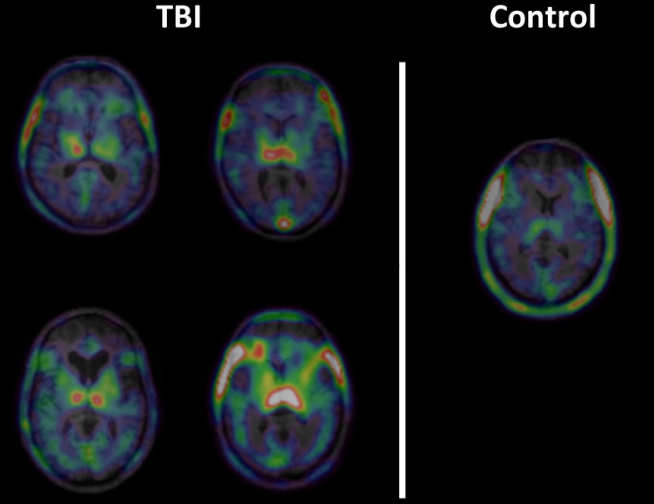

In collaboration with the Ministry of Defence and the Royal College of Surgeons of England we are investigating the effect of blast on the brain. Participants are soldiers who have suffered a blast traumatic brain injury (bTBI) as a result of improvised explosive devices (IEDs) in Iraq and Afghanistan. This study is using positron emission tomography (PET) and magnetic resonance imaging (MRI) to investigate chronic neuroinflammation and neurodegeneration and its relationship to brain structure and function. This is the first PET study investigating neuroinflammation following blast trauma in a military population and will inform our understanding of blast-related neuropathology in future conflicts.